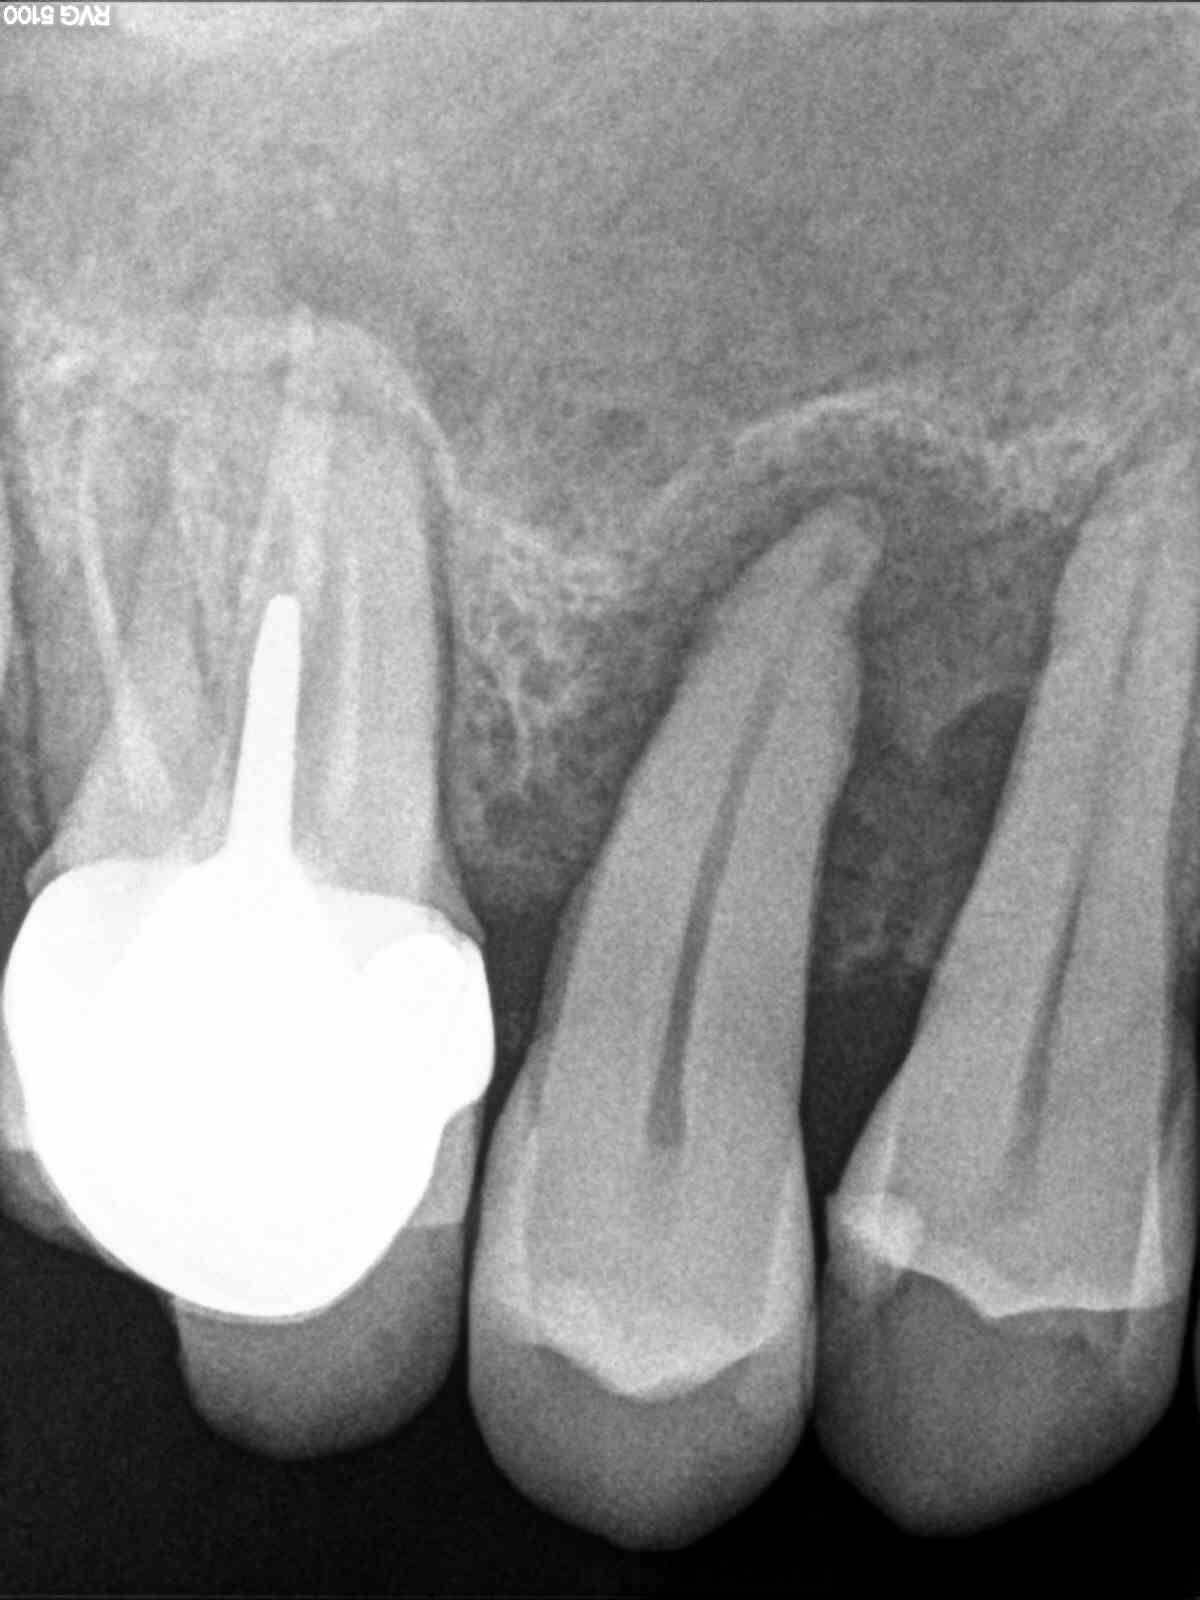

Un jolis cas pour le paro ou l'implanto avec une 15 qui gigote bien comme il faut.

Pas d'os, pas de racines.

Elle est vivante ?

Et sinon de l'os je dirais qu'il en reste mais déminéralisé sauf si tu as trouvé une perte au sondage localisée.

Au niveau oclusion elle dit quoi?

La 6 paraît douteuse....

Infection sous la 6 non symptomatique, douleur sur la 5 qui amène à la consultation en urgence et demande d'un panoramique pour voir la situation en global. Patient venant au départ avec une idée d'extraction.